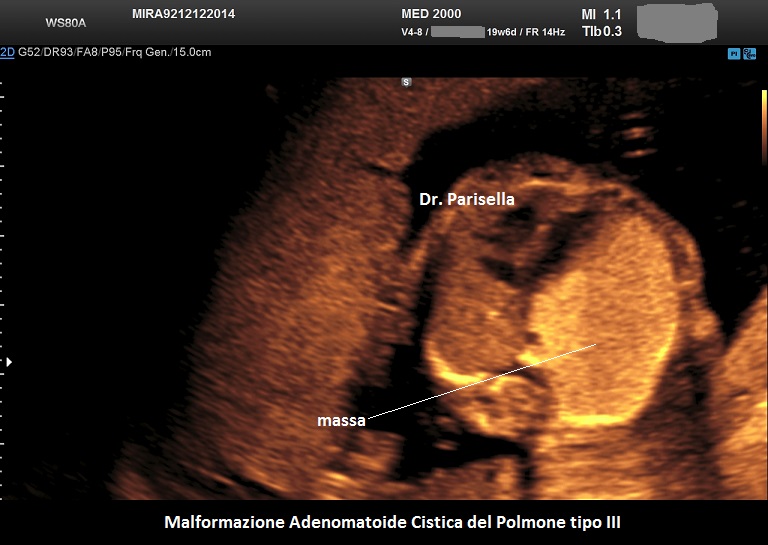

MACP tipo III: è una massa solida che contiene cisti molto piccole < 0,5 cm.

. Il tipo III è una massa solida che contiene cisti molto piccole (< 5,0 mm). (Rolo LC et al., 2022).

Si presenta come una massa occupante spazio di solito unilaterale in più del 95% dei casi e solitamente coinvolge un lobo o segmento del polmone; nella sua evoluzione determina dislocazione del mediastino e del cuore. L'ecostruttura distingue due forme: una forma multicistica  caratterizzata dalla presenza di multiple cisti di varia grandezza (tipo I e II) e una forma microcistica (tipo III) corrispondente alla variante solida.